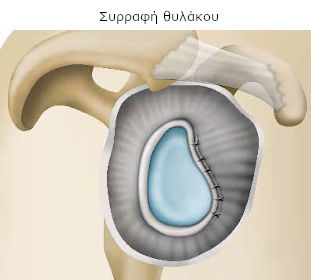

- είτε τη συγκράτηση του σάκου που περιβάλλει την άρθρωση (θύλακος) ή/και του επιχειλίου χόνδρου και την επανακαθήλωσή τους στην αρχικής του θέση, όσο είναι δυνατό. Είναι η τεχνική που παρουσιάζεται εδώ και φέρει το όνομα «Bankart».

Ο χειρουργός σας συγκρατεί και επανατοποθετεί το σάκο που περιβάλλει την άρθρωση (θύλακος) ή/και τον επιχειλίο χόνδρο. Στη συνέχεια προχωρεί στη συρραφή, με μέθοδο της επιλογής του.

Ο χειρουργός αποσπά το θύλακο που περιβάλλει την άρθρωση και ανάλογα με τις βλάβες που διαπιστώνει, διατήρει το μέρος εκείνο που προσεγγίζει τη φυσιολογική του μορφή. Μόλις τον επανατοποθετήσει στη θέση του, προχωρεί στη συρραφή για να τον σταθεροποιήσει στην κεφαλή του βραχίονιου.

Υπάρχουν διάφορες μέθοδοι συρραφής (βίδες, ράμματα, άγκυρες κτλ). Τα υλικά που χρησιμοποιούνται, συνήθως δεν αφαιρούνται, καθώς είναι πολύ μικρά ή απορροφούνται από τον οργανισμό (απορροφήσιμο υλικό).